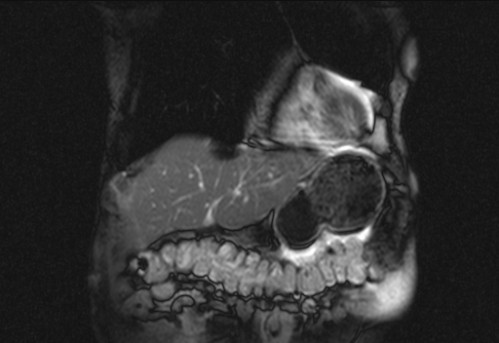

Auffälliges Abdomen bei der Vorsorgeuntersuchung einer älteren Dame

ICD: C64

68 Jahre alte Frau. Sie geht zur Darmspiegelung im Rahmen ihrer Krebsvorsorgeuntersuchung. Der Internist bemerkt bei der ergänzenden sonografischen Untersuchung des Abdomens einen auffälligen Befund.